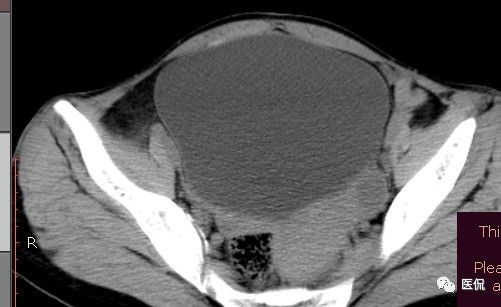

腹腔内残留的纱布在人体内引起渗出或液化坏死并纤维包裹形成异物性脓肿(纱布瘤)。纱布瘤的影像特点:圆形或卵圆形肿块,较大,有完整包膜,薄壁,较少的情况下为厚壁,边界较完整,增强后薄膜可以持续强化。不同时期的纱布瘤可以有不同表现:早期(10个月或半年内)多表现为蜂窝状;2~5年内一般表现为囊性飘带状;10~20年之后则为实性软组织密度,包膜钙化呈钙化网状结构。手术过程中残留在人体内的医用纱布所形成的肿瘤样病变。

腹腔内遗留纱布团的影像学表现,以B超较具特征性,其主要表现为:腹腔或盆腔内特殊率减的黑色包块,后方伴有扇形衰减的声影,上窄下宽,好似一“黑色大布”,早期包块内含有不规则光团或光点,随时间延长有缩小或消失,为纱布团内气体。CT的优势在于早期常表现为软组织密度的肿块,其内可见多少不等的气泡,随时间的延长气泡逐渐被吸收减少至消失,增强扫描可见包膜不同程度强化而内容物无强化。熟悉其影像学表现,可在术前作出明确诊断。